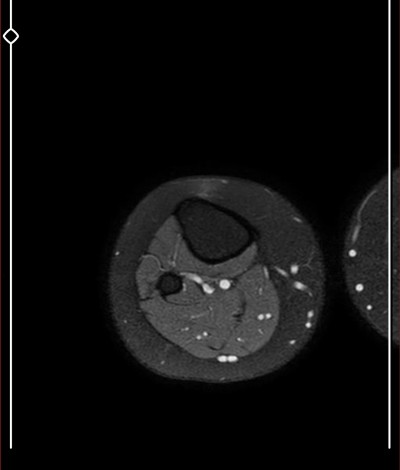

Kızlar çok önemli benim için aşırı şekilde dizlerim ağrıyor böyle çıktı

Mr sonucunu yazılı olarak birkaç güne alabilirsin tatlım biz bilemeyebiliriz sonuçta aramızda ortopedisyen yok  eşimdede sağlam bacakta tümör çıktı  3 cmlik o yüzden raporun çıkmasını bekle bence

Burada ortopedi hekimi yada radyoloji uzmanı yoksa bu görüntüleri kimse yorumlayamaz.Doktora sorulacak sorular bunlar